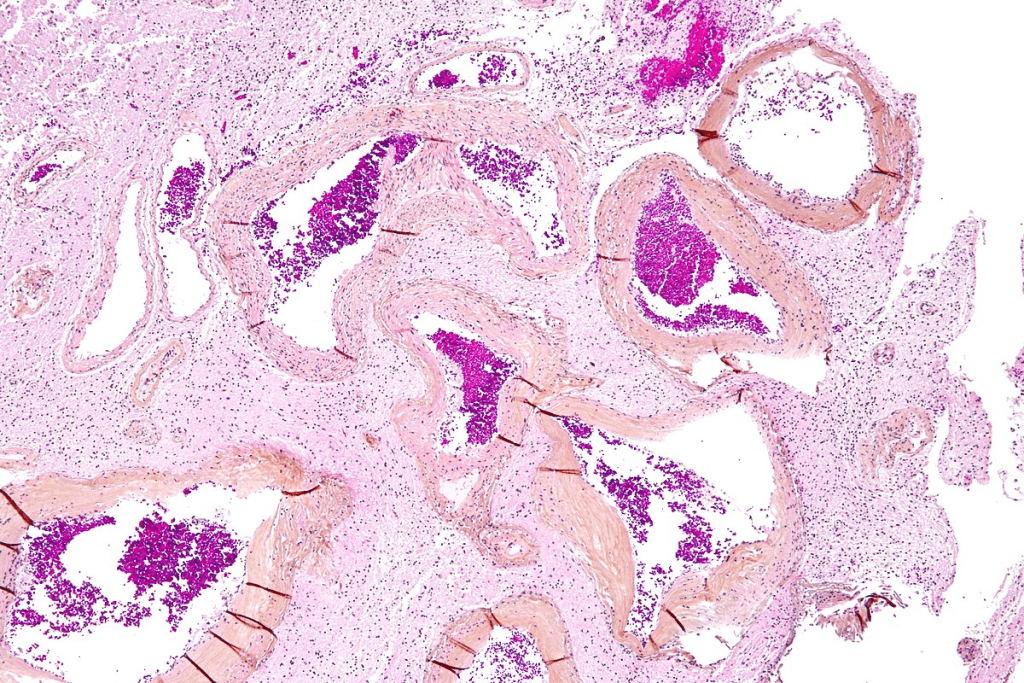

The Pathophysiology of Vascular Malformations

The exact cause of angiodysplasia is not fully understood. It’s thought to be linked to aging and the degeneration of small blood vessels in the colon. This can cause abnormal blood vessels to form, which are more likely to bleed. It’s also connected to heart and lung diseases, showing it’s a complex issue.

Angiodysplasia is most often found in the right colon, like the cecum. The cecum’s size and tension might make it more prone to this condition.

The condition’s hallmark is dilated, thin-walled blood vessels. These are at risk of rupturing and causing bleeding.